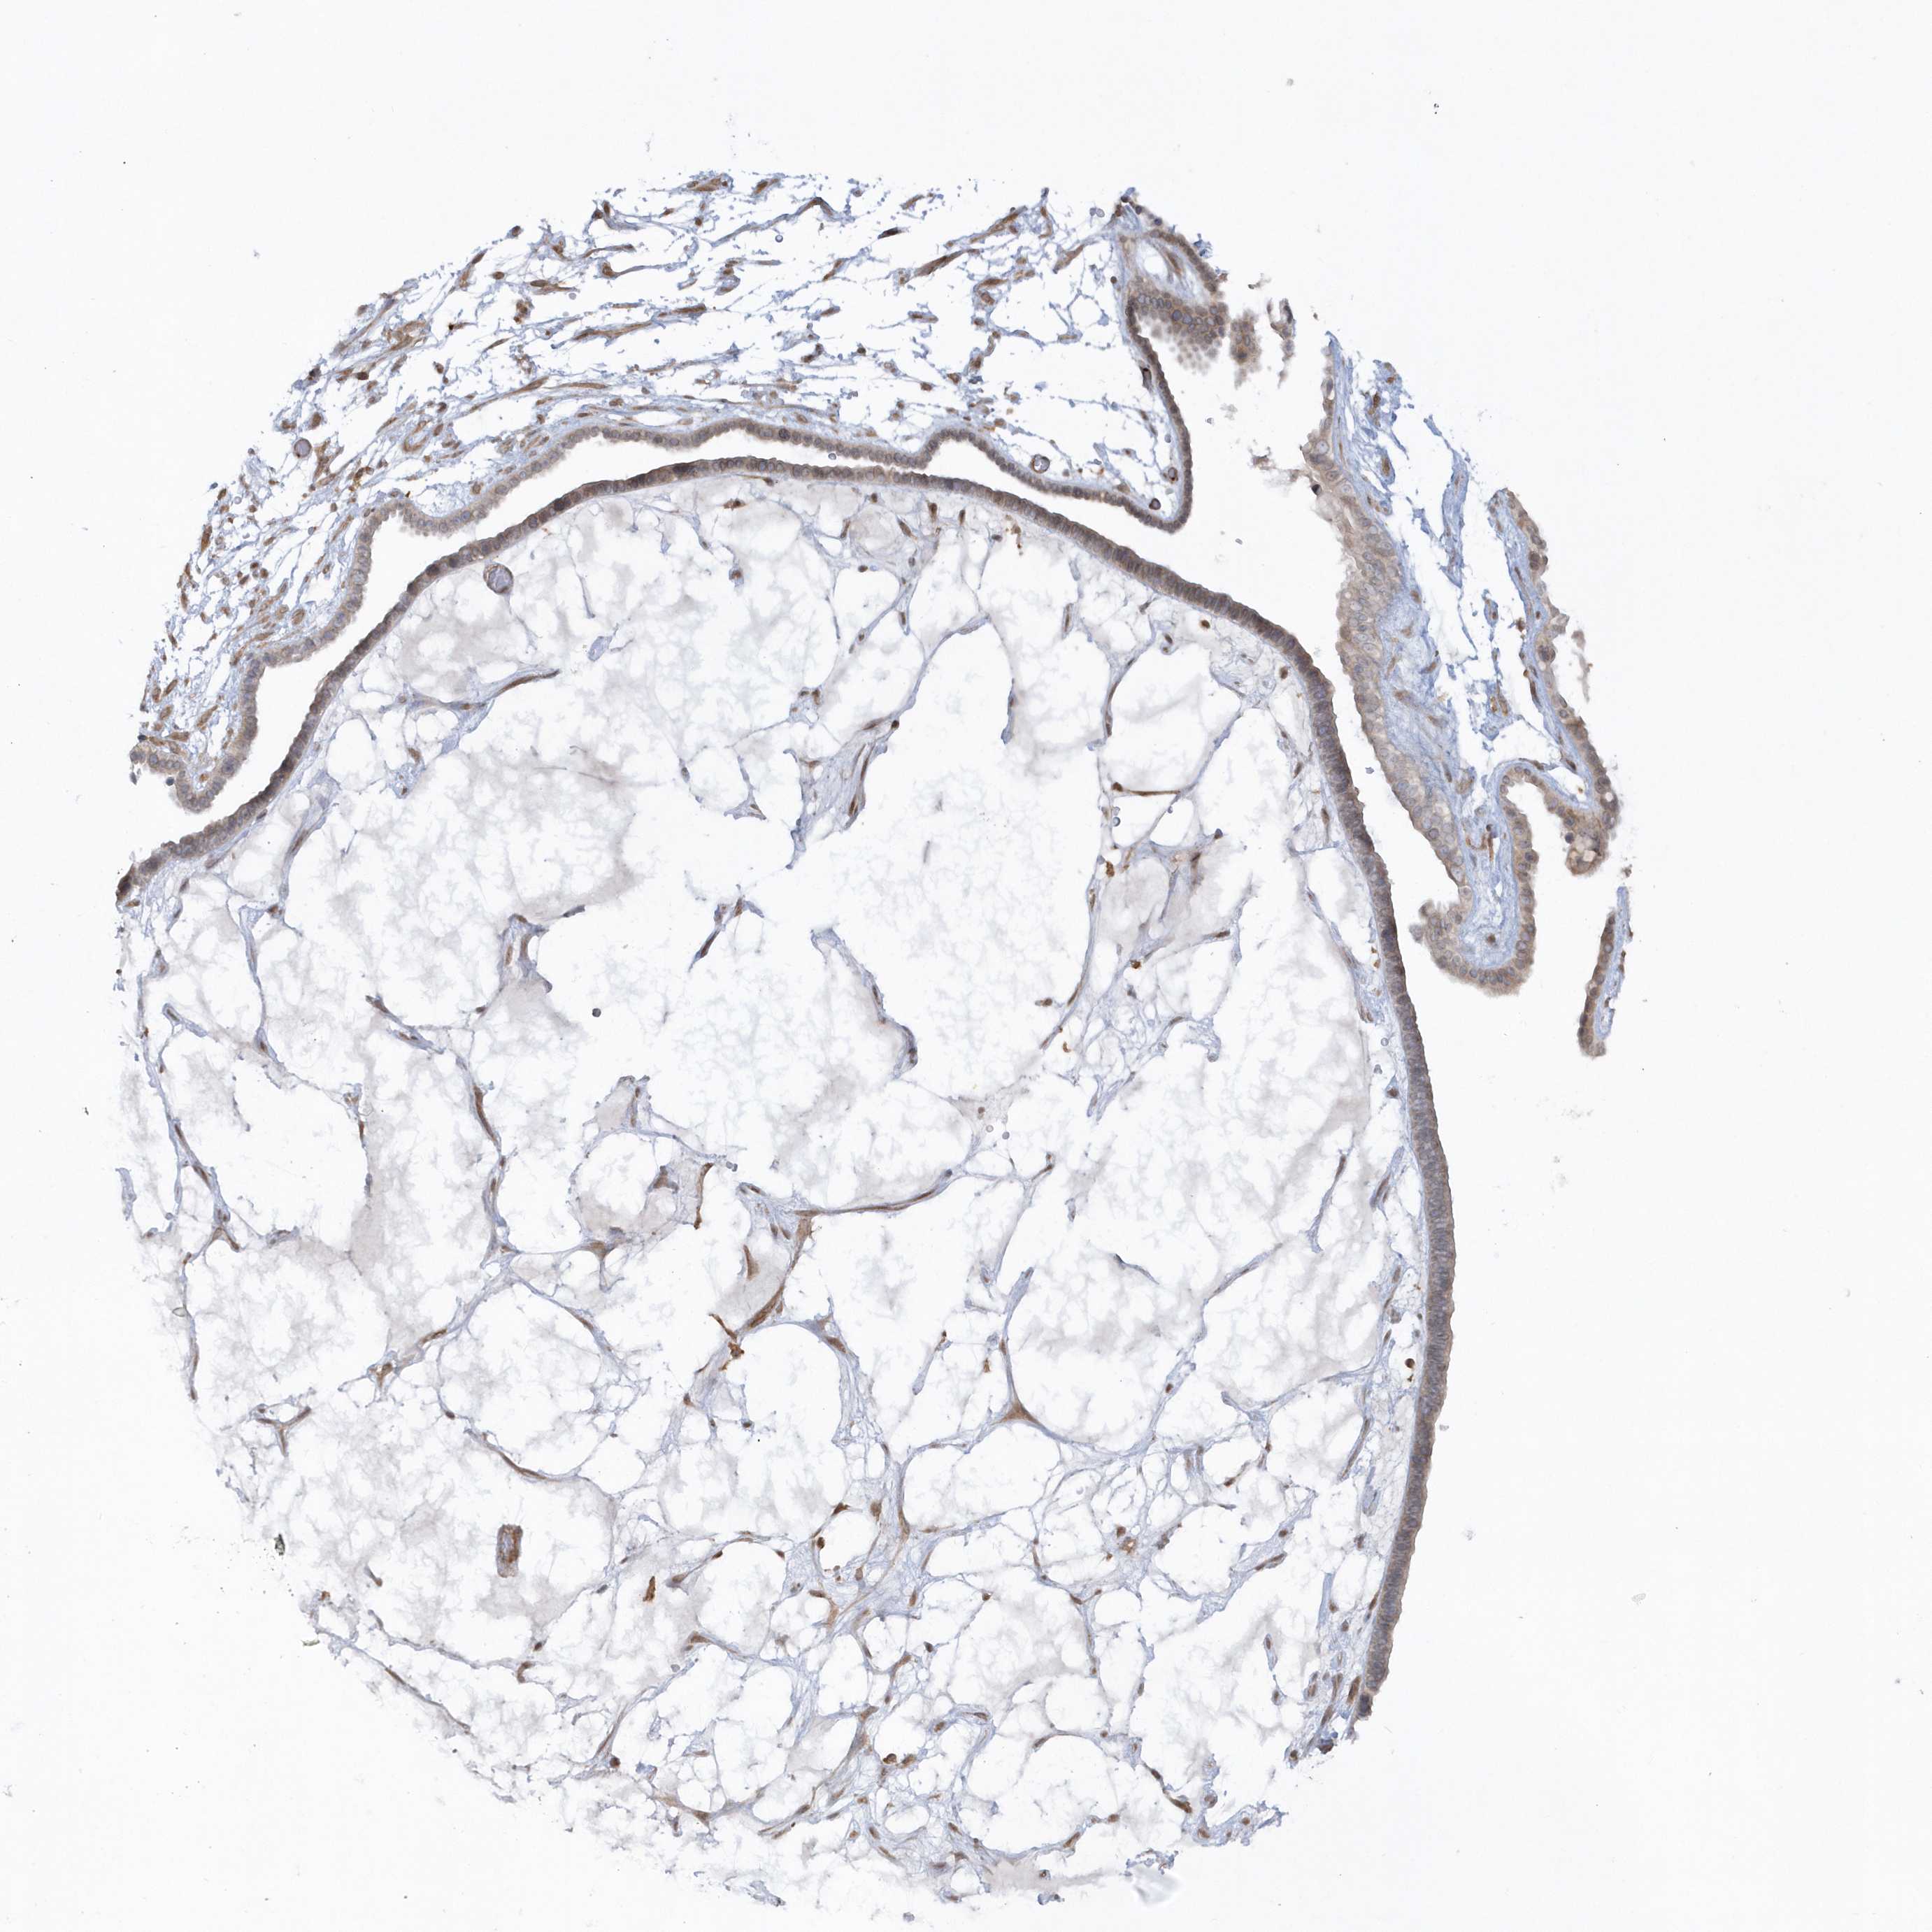

OVARIAN CANCER - Protein expressioni

A mouse-over function shows sample information and annotation data. Click on an image to view it in a full screen mode. Samples can be filtered based on level of antibody staining by selecting one or several of the following categories: high, medium, low and not detected. The assay and annotation is described here.

Note that samples used for immunohistochemistry by the Human Protein Atlas do not correspond to samples in the TCGA dataset.

Antibody stainingi

Antibody staining in the annotated cell types in the current human tissue is reported as not detected, low, medium, or high, based on conventional immunohistochemistry profiling in selected tissues. This score is based on the combination of the staining intensity and fraction of stained cells.

Each image is clickable and will lead to virtual microscopy that enables deeper exploration of all samples and also displays staining intensity scores, fraction scores and subcellular localization as well as patient and tissue information for each sample.

Antibody HPA034757

Cystadenocarcinoma, serous, NOS

Carcinoma, endometroid

Cystadenocarcinoma, mucinous, NOS

Carcinoma, NOS